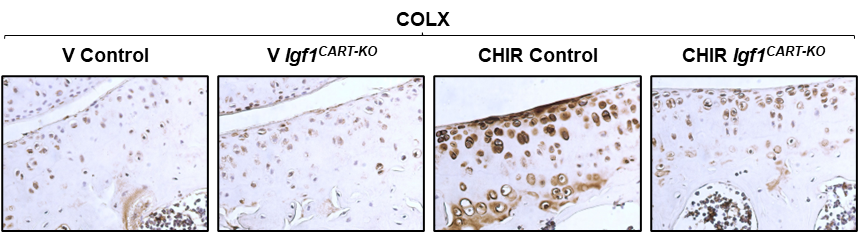

This finding was exciting because it directly linked IGF1 to OA progression. Specifically, we found that IGF1 was responsible for inducing chondrocyte hypertrophy—a process where cartilage cells lose their normal identity and produce a different type of matrix and tissue-destructive enzymes, thereby leading to cartilage breakdown.

By blocking IGF1, we did not only reduce chondrocyte hypertrophy but also prevented the formation of osteophytes—bony outgrowths that are characteristic of OA. In addition, markers of cartilage degradation, such as the enzymes MMP13 and ADAMTS5, were significantly lower in Igf1-deficient mice. Combined, these data provided compelling evidence that IGF1 plays a central role in joint degeneration when Wnt signaling is overly active.